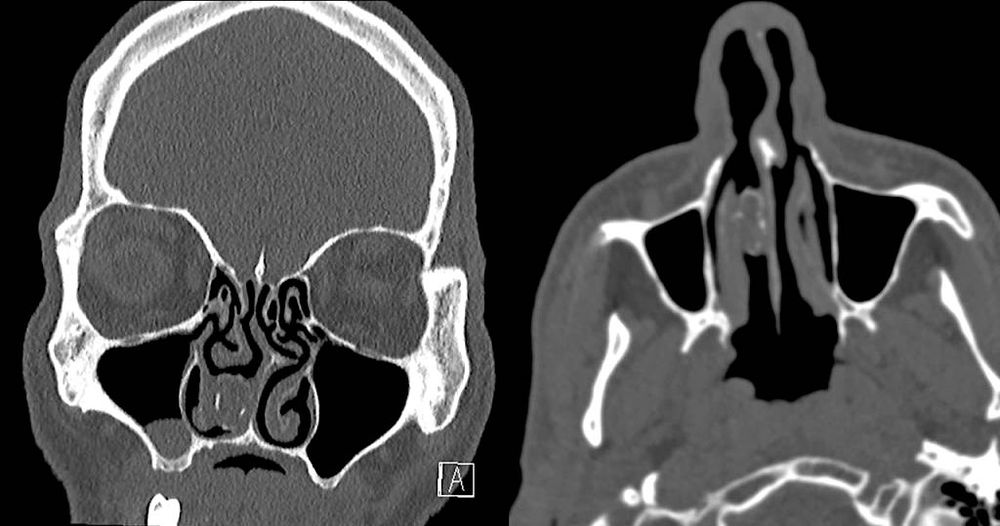

Selon un rapport publié le 25 octobre dans le journal BMJ Case Reports, l’homme de 48 ans avait été admis à l’hôpital Westmead de Sydney, en Australie, après s’être plaint de maux de tête. Un scanner de son crâne révéla une "masse grise solide" dans la cavité nasale droite. Lors d'un interrogatoire, l'homme affirma qu'il avait eu des infections nasales récurrentes et qu'il avait déjà remarqué une obstruction des narines.

Les médecins ont qualifié la masse de "rhinolithe" (littéralement "cailloux de nez"). Les rhinolithes sont des concrétions calcaires qui se forment lentement dans les fosses nasales, autour d'un corps étranger.

Cela signifiait donc que du calcium et d'autres minéraux s'étaient accumulés autour d'un "corps inconnu" dans la cavité nasale de l'homme. Ils ont alors retiré le bouchon obstruant la narine du patient et ont découvert qu'il s'agissait d'une "capsule de caoutchouc contenant des matières végétales en dégradation". Soit, en d'autres termes, un vieux ballon rempli de cannabis.